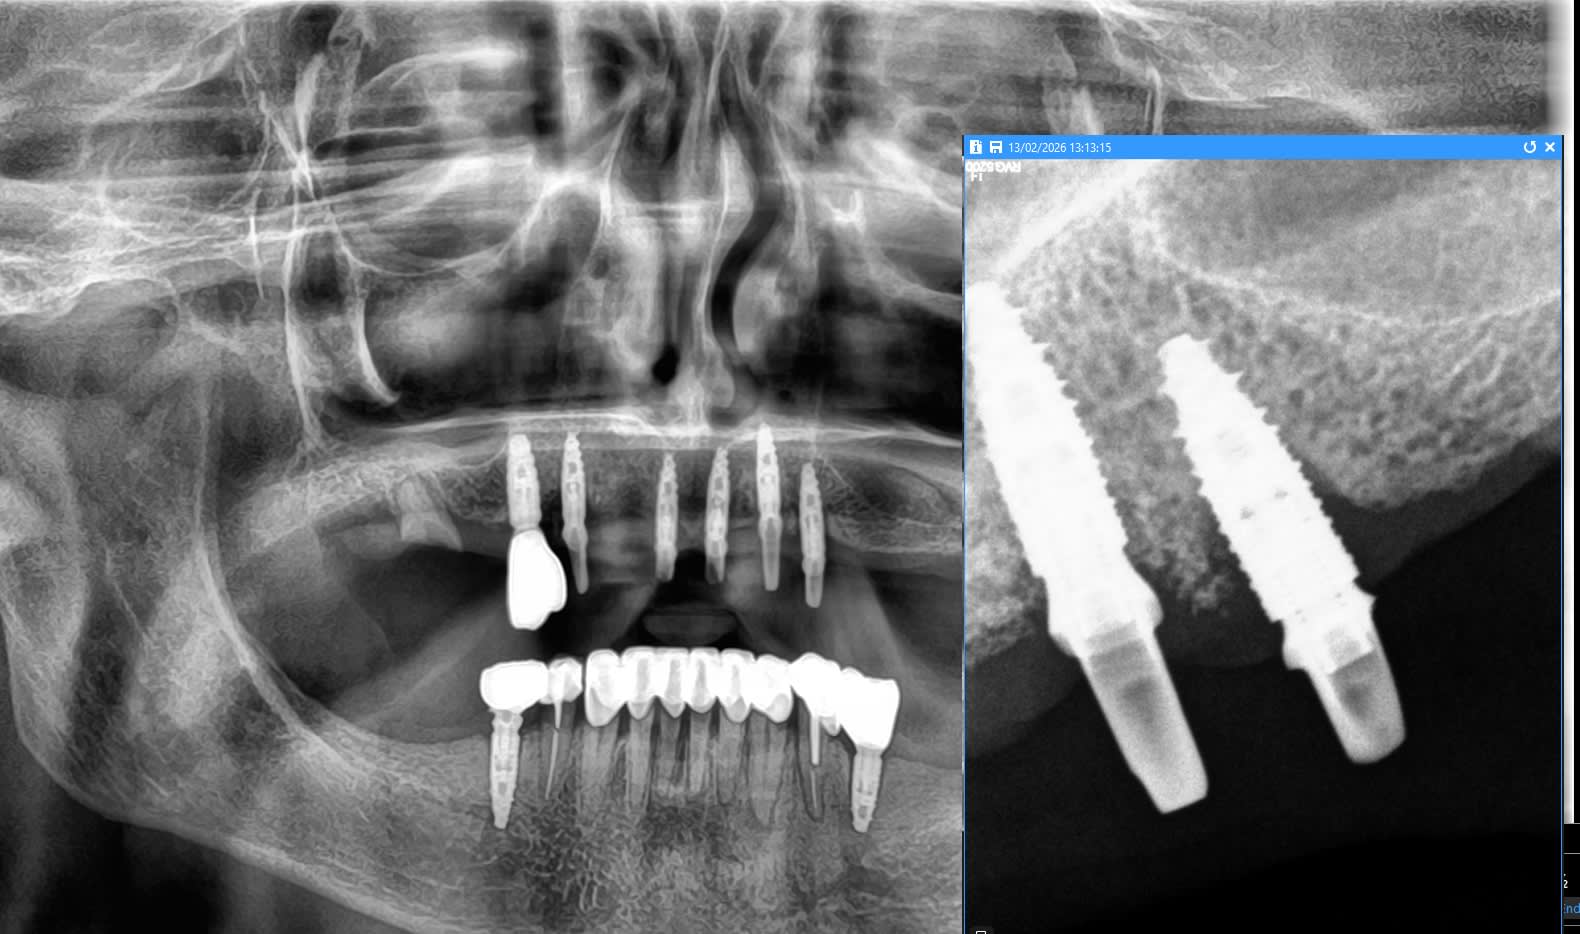

avez-vous une idée de la marque des implants utilisés au maxillaire.

Biotech kontact